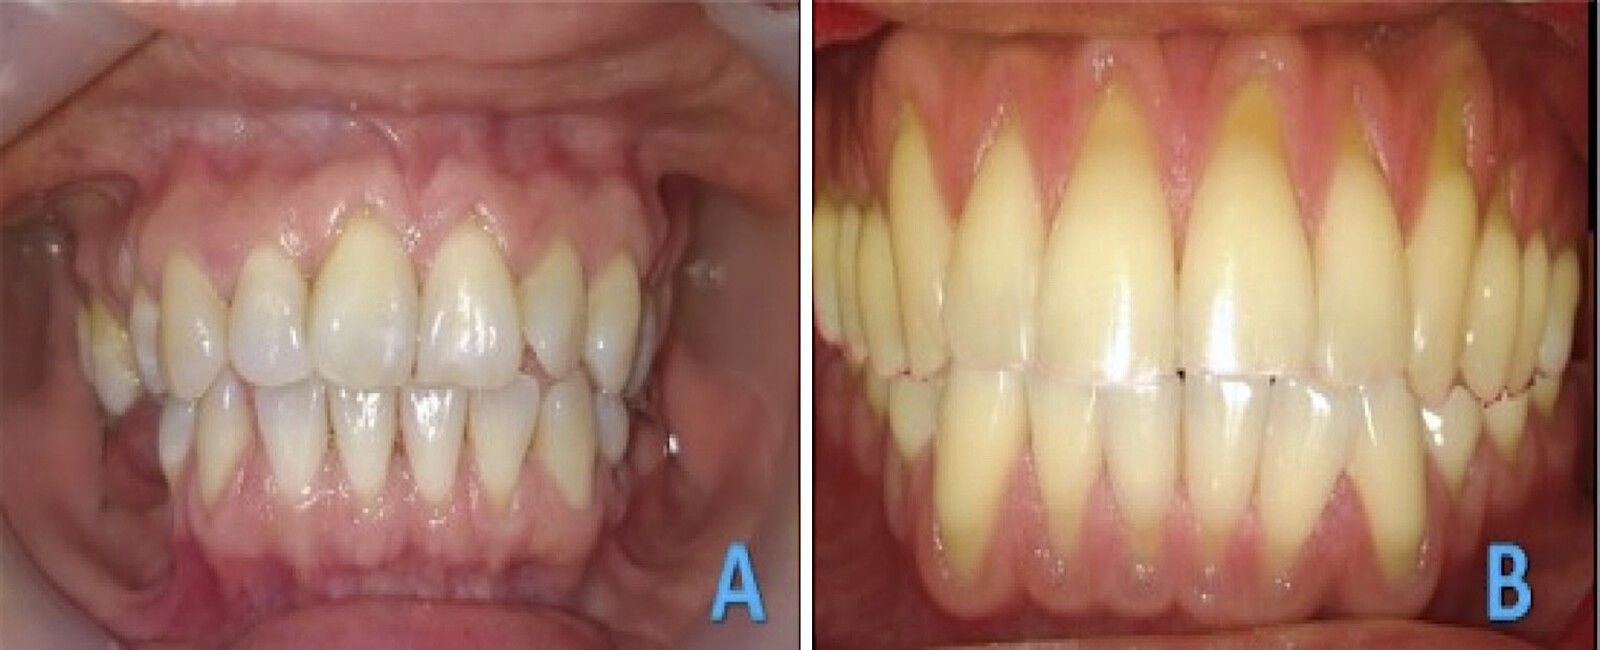

Figura 5. A) Paciente de 30 años con LCNC masivas (SPNC). B) Paciente de 32 años con serie de dramáticas recesiones vestibulares. Ambos reportan bruxópatia y dieta acida.